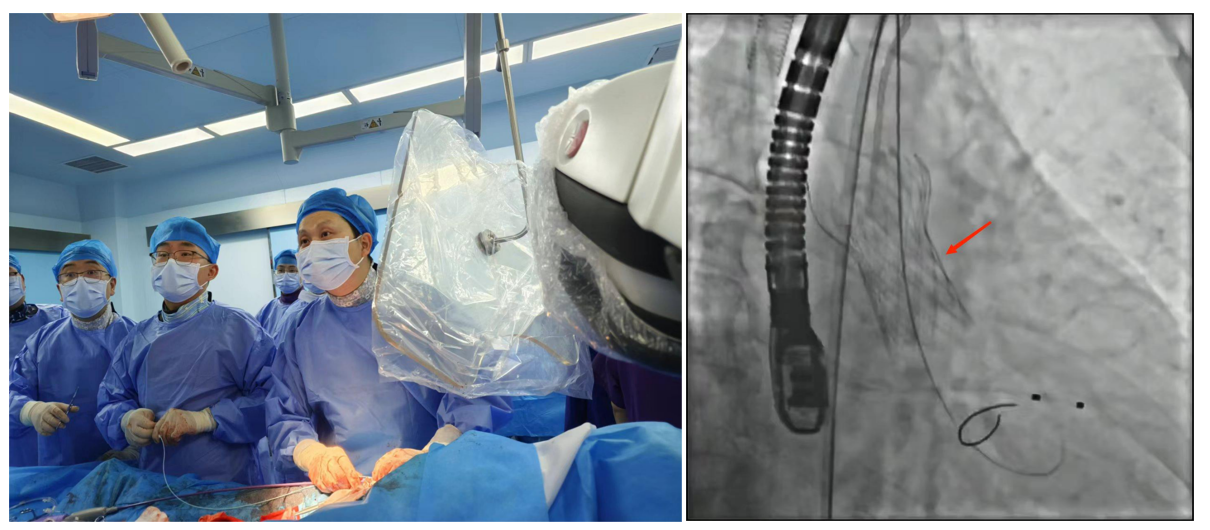

1.經皮冠狀動脈介入治療(PCI):是用心臟導管技術疏通狹窄甚至閉塞的冠狀動脈管腔,從而改善心肌血流灌注的一組治療技術。在血管嚴重狹窄或閉塞病變段放置支架或藥物球囊,以保證血管長期暢通,是冠脈介入手術的主流。

f4d740e1d5b64bd7945f05bce7d78af0.Png

經皮冠狀動脈介入治療(PCI)